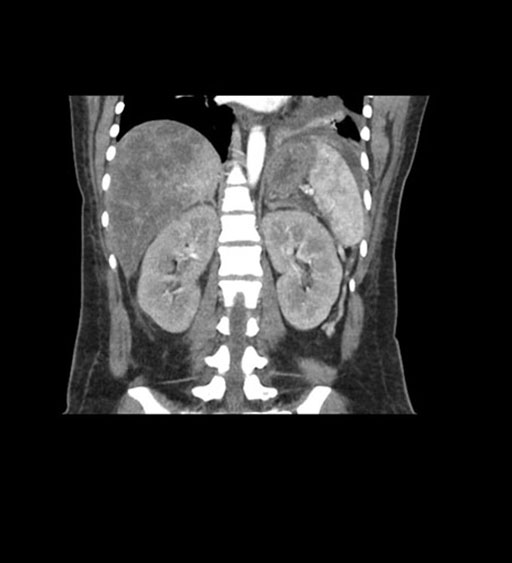

Coronal Arterial

Coronal Venous